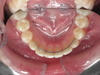

Il faut alors rendre la canine visible : Un dégagement chirurgical et un collage d’une attache sont pratiqués sous anesthésie locale ou générale dans les cas difficiles. Cette attache est reliée au reste de l’appareil pour que la traction et le guidage s’installent. Le déplacement, c'est-à-dire la mise en place de la canine, se fait doucement au rythme orthodontique et il faut entre 6 et 12 mois pour la positionner correctement. Un petit pourcentage de canines refusent de bouger : Elles sont " ankylosées c'est-à-dire soudées à l’os et il faut les extraire pour les remplacer par un implant". Impossible de le savoir à l’avance ! Il faut donc toujours essayer de les tracter : « 100% des gagnants ont tenté leur chance ».

3e radio : Fil de traction posé sur la canine